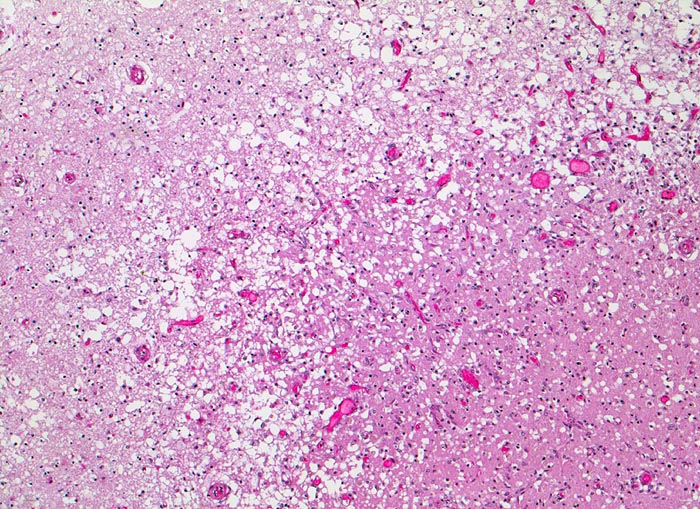

PathoPic ID 3524 - anämischer Hirninfarkt

anämischer Hirninfarkt

vaskulär / Durchblutungsstörung

Hirn parietal

Nervensystem

Randbereich des Infarktes mit

spongiotischer Auflockerung des Hirnparenchyms,

Gefässneubildungen und unscharfer Mark-Rinden Grenze. In der helleren

Rinde links im Bild sind keine Neuronen sichtbar.

Vor 7 Tagen Entwicklung eines Hemisyndrom links.

Histologie

50

87